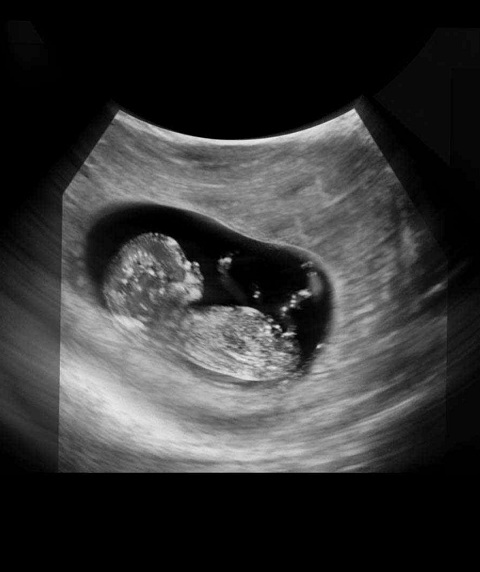

胎儿图

B超图

现在胎儿从牙胚到趾甲,身体的雏形已经发育完成了。开始长在头部两侧的眼睛距离渐渐地拉进,移到了脸部,耳朵也已经到达最终的位置。

胎儿的手指和脚趾已经完全分离,一部分骨骼开始变得坚硬,并出现关节雏形。胎儿的肠子最近生长得非常快,有一部分进入脐带里,现在它们开始要转移到腹腔内。他的肾正在向膀胱分泌尿液。

胎儿的神经细胞增殖迅猛,而且神经突触(大脑中的神经线路)正在形成。你的宝宝现在可能已经有了更多的反射动作,包括吮吸,如果你用手戳戳肚子,他甚至会动一动,不过,几周之内,你还无法感觉到他的活动。